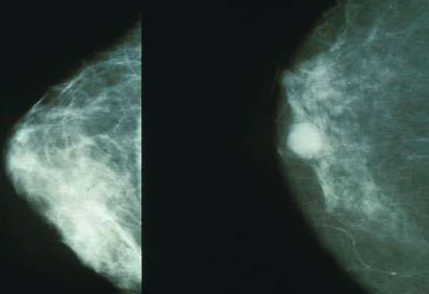

據(jù)出國看病服務(wù)機構(gòu)厚樸方舟了解,近日一項研究報告發(fā)現(xiàn),有潛力誘發(fā)乳腺癌的細菌通常存在于癌癥患者的乳腺中;而如果個體健康乳腺中含有大量的有益細菌,這些細菌則會保護女性免于癌癥的發(fā)生;相關(guān)研究或可幫助科學(xué)家們利用益生菌來保護女性免于乳腺癌的發(fā)生。

研究人員對經(jīng)歷病灶切除術(shù)、良性(13名女性)或癌變(45名女性)乳房切除術(shù)的58名患者進行研究,對患者機體的乳腺組織進行研究分析,同時以23名接受乳房縮小術(shù)或增大術(shù)的健康女性為對照進行研究;研究者利用DNA測序?qū)M織樣本中的細菌進行鑒別,并且培養(yǎng)從而確定所存活的細菌。